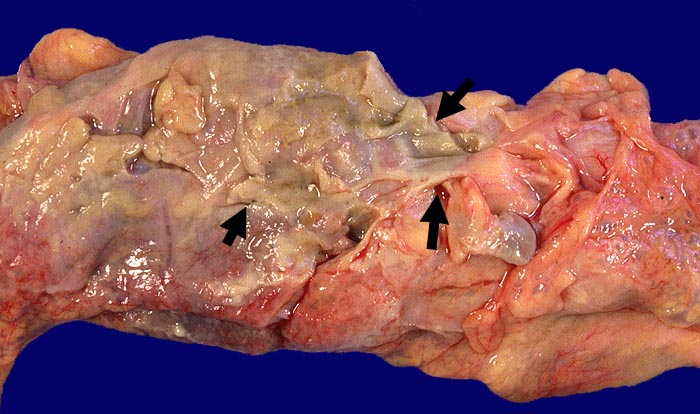

AP/ Divertikulitis

Divertikulitis

Darm, Anus

Kolon Sigma

Makroskopie

Befund

Pathologischer Befund